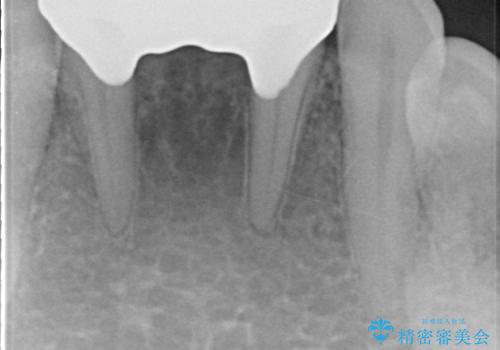

- 前歯の保険のブリッジが欠けてしまっているのを治したいとのことでした。

前装冠が剥がれていて、下の金属が見えてしまっていました。

保険のブリッジは入れてすぐ欠けてしまったのを長年使用していたとのことです。

かみ合わせもきつく、ジルコニアクラウンではセラミックでも欠けてしまいそうでした。

今回は、丈夫な欠けにくいフルジルコニア(ヴェレッツァ)クラウンでブリッジにすることにしました。